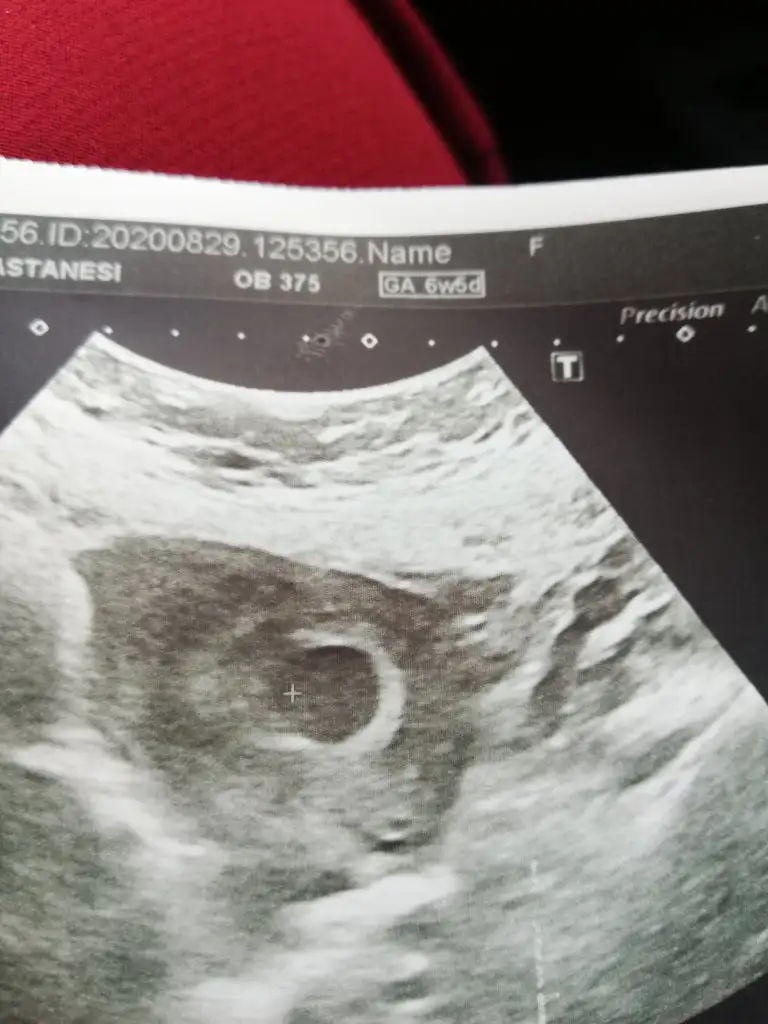

Arkadaslar ya bu erken ultrason resimlerinden cinsiyetinden anlayan arkadaslar vardi baska forumda okumustum. Varmi acaba 2 oglum var 3uncuye hamileyim. bu Lavabo acici testini yaptim kiz gosteriyo.